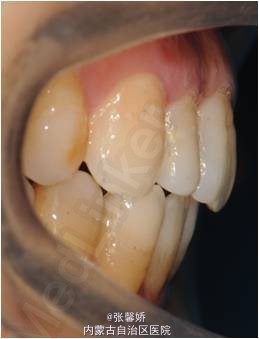

诊断 处理

牙列中度拥挤;A2、D4反合 处理:时代天使隐形矫治器矫治 拔除C8、D8 适当下前牙邻面去釉 排齐整平上下牙列,改正A2、D4反合 治疗时间2年左右,矫治后牙齿排列整齐,咬合关系良好,患者满意。